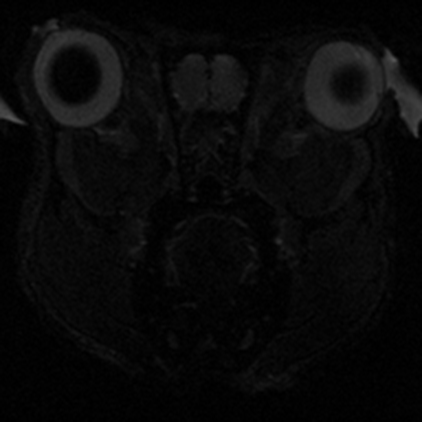

Yüksek sinyal (SNR) ve güçlü gradyan sargıları ile daha yüksek uzamsal çözünürlük ile görüntüleme yapılmasına olanak tanır. Böylece daha deney hayvanlarında çok daha olan küçük anatomik yapılar ve bunların detayları daha net görülür, bu da beyin, kalp, batın ve kas-iskelet yapılarının görüntülenmesinde sistemi özellikle değerli kılar.

Yüksek manyetik alan gücü, daha küçük gantri çapı ve özelleşmiş hayvan sargıları (koil) sinyal-gürültü oranındaki iyileşmeye katkıda bulunur. SNR’daki bu iyileşme daha kaliteli görüntülere ve hassas patolojik değişimlere daha yüksek duyarlılığa olanak tanıyabilir. Daha yüksek SNR görüntüleme süresini kısaltabilir. Ayrıca fMRI, dinamik kontrast ve kardiyak sekanslar gibi yüksek zaman çözünürlüğünün önemli olduğu protokollerde avantajlıdır. Doğaları gereği düşük SNR sorunları olan difüzyon ağırlıklı görüntüleme ve difüzyon tensör görüntüleme gibi protokollerde de önemli iyileşmeler sağlar.

7T MRG tarayıcısının sağladığı yüksek doku görüntü kontrastı organlardaki farkı doku tipleri ve dokulardaki varyasyonları ayırt etmek için önemlidir. Bu, özellikle nöro-görüntülemede örneğin hipokampüs ve bazal ganglia gibi yapılar için avantaj sağlar.